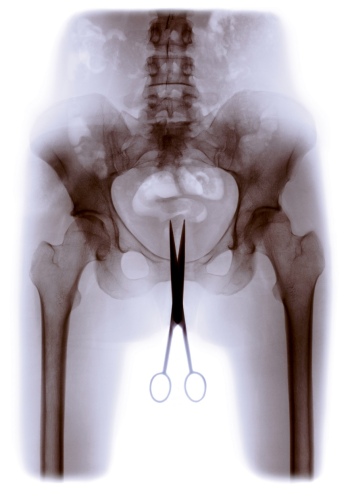

Cris Bierrenbach, Série Retrato Íntimo (Tesoura), 2003 © Courtesy the Artist